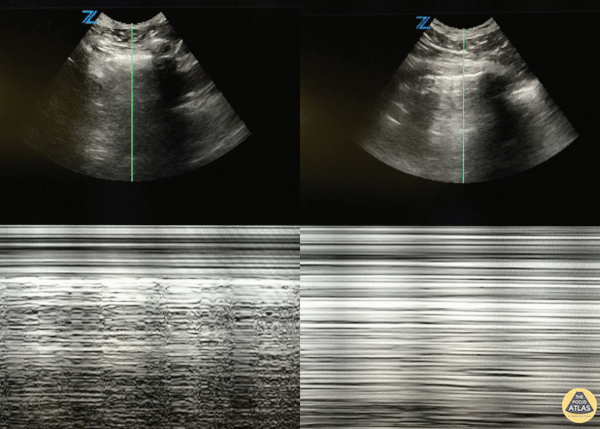

46 y/o M with 20 pack year smoking history with sudden onset right sided chest pain that woke him from sleep. Decreased breath sounds on right side. POCUS with decreased lung slide (right of image) with normal lung slide in left lung (left side of image). Lung slide can often be appreciated by watching the pleural surfaces move along each other but if you're uncertain, putting the US in m-mode and looking for the classic "seashore sign" (left image) versus the "barcode sign" (right image) can help you figure it out. Dr. Eric Roseman - Resident Physician, Kings County Emergency/Internal Medicine